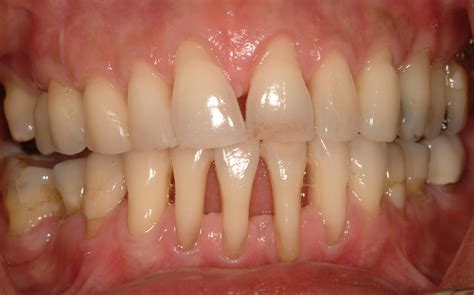

Periodontal disease is a silent, inflammatory condition that affects the tissues surrounding and supporting your teeth. It typically begins as gingivitis, characterized by inflammation, and can advance to periodontitis, which involves the destruction of bone and connective tissue. By examining Gum Disease Pictures, you can often identify the transition from healthy, firm, pink gums to tissues that appear puffy, red, or even receding.

• Recession: Notice how the gum line moves away from the crown, often making teeth look longer.

• Swelling: Observe how the interdental papilla (the triangle of gum between teeth) loses its sharp point and becomes rounded or blunted.